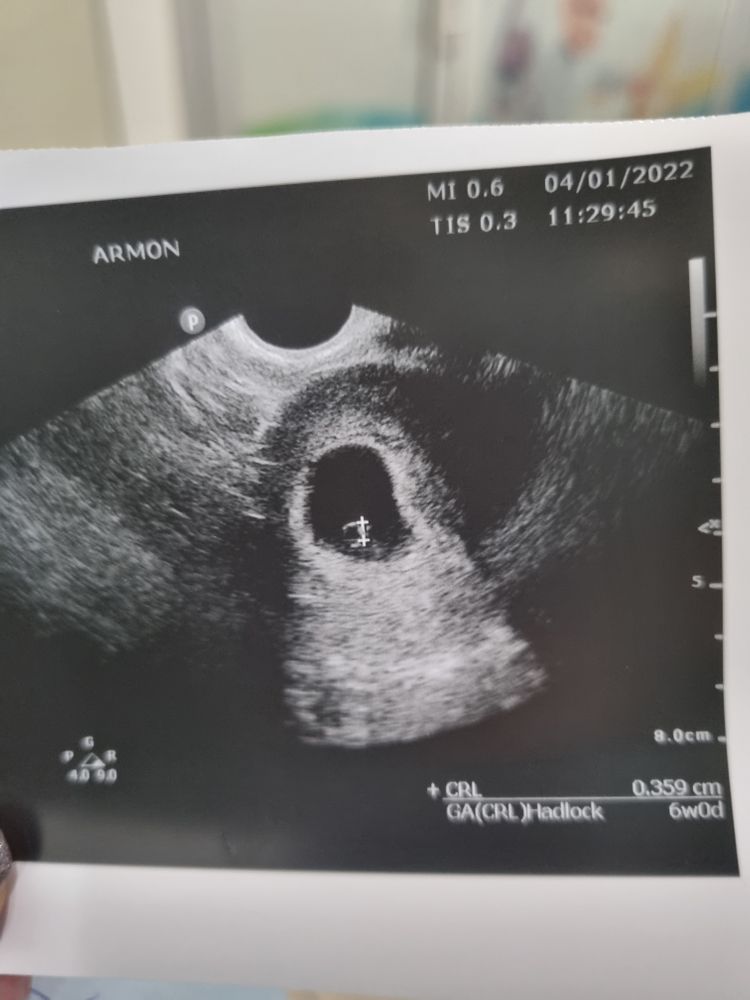

Буду трижды мамой в этом году в Зачатие 4 года Когда виден эмбрион Фолликулометрия Девочки, при каком размере плодного яйца у вас увидели эмбрион? Посмотрите еще 20 записей на эту тему Отменить Ответить Марина В 6+2 пя было 19 мм,ктр 5,4 мм 07.02.2022 Ответить RM При пя 14 мм был эмбрион 6,4 мм. Срок был 6+3. 07.02.2022 Ответить Яна Я не знаю, при каком размере пя, но по срокам 5+3 по месячным, 6 по узи (ранняя овуляция) 07.02.2022 Ответить ДФ 17 мм УЗИ на какой ДЦ Чаты Беременных Выберите чат: Январята-2026 Февралята-2026 Мартята-2026 Апрелята-2026 Майчата-2026 Июнята-2026 Июлята-2026 Августята-2026